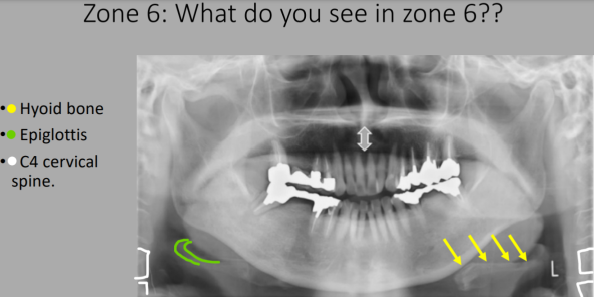

What Zone Is This?

Zone 6: Hyoid Bone

What do we see in Zone 6?